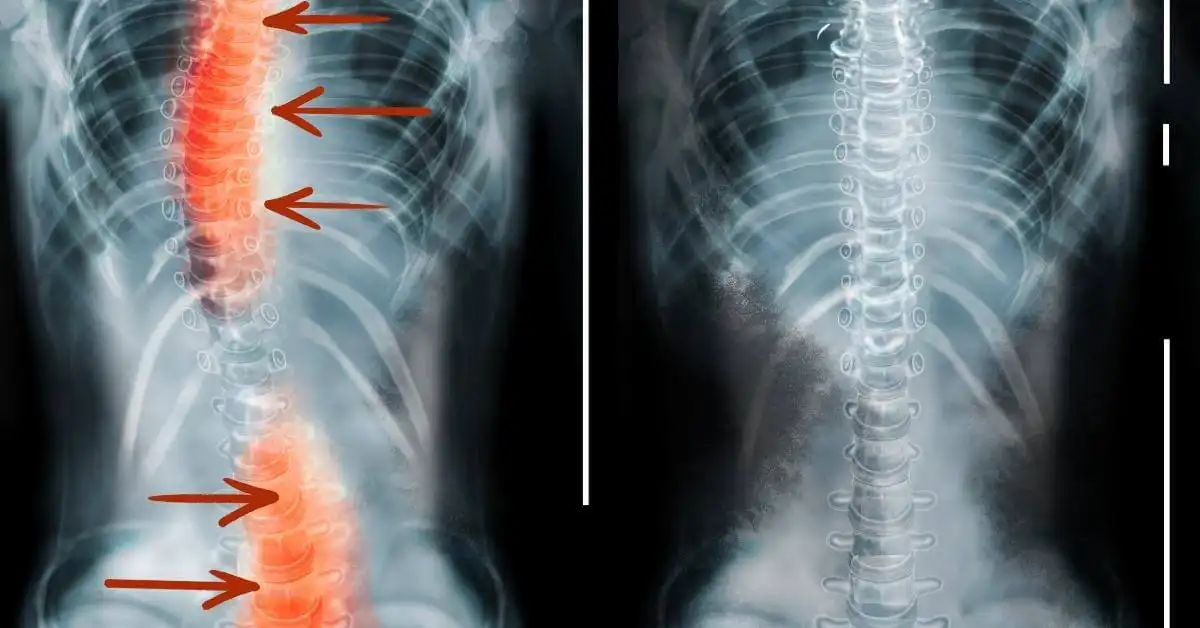

X-rays are used to show and allow measurements of the curve in the spine. X-rays are taken from the front and sides. Magnetic resonance imaging (MRI) scans or CT scans may be used to provide more detailed images.